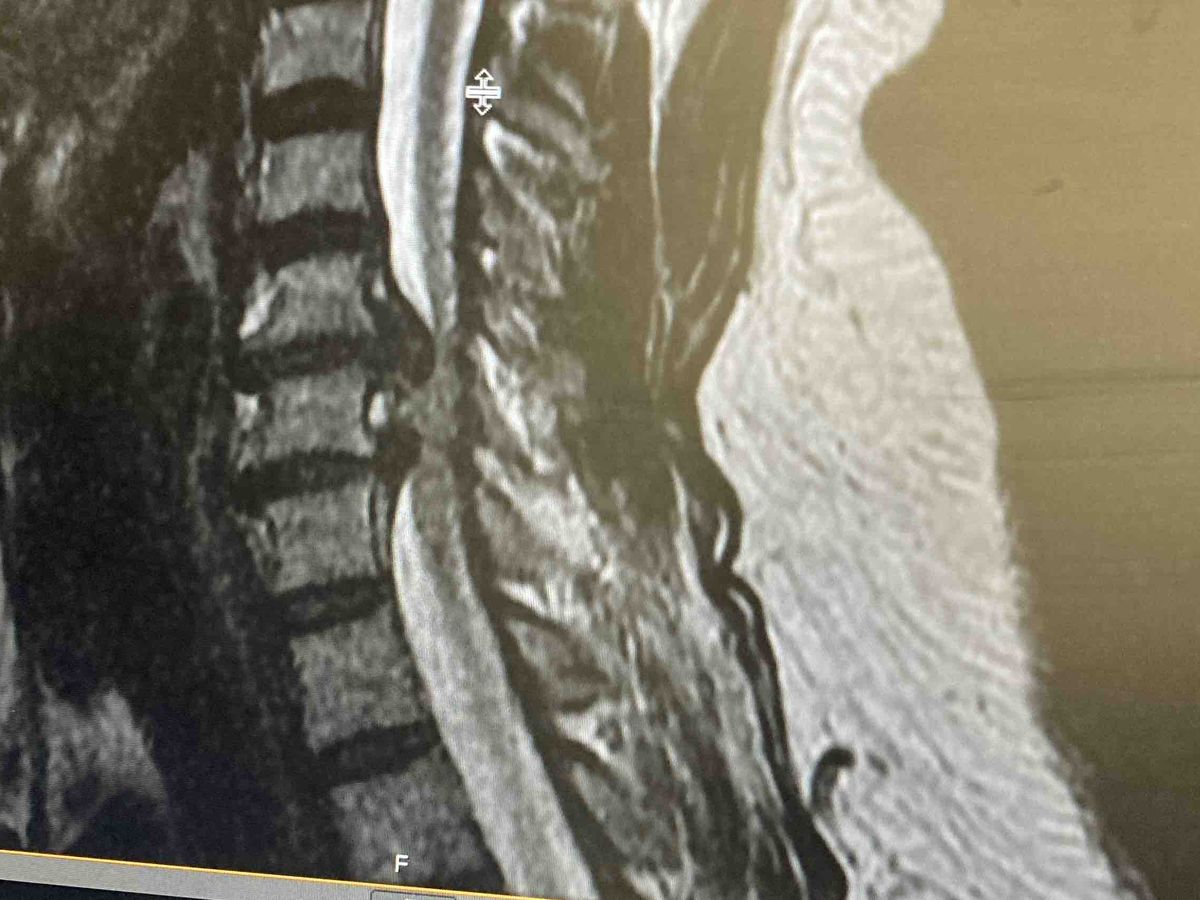

Nicole loves to serve, serve God’s people, serve our community, serve when and where she can! Nicole is currently in a hospital for an emergency surgery on her spine. She pays her bills by working everyday and she will not be working for a little while due to a medical emergency!